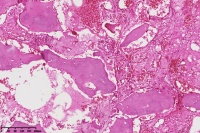

右胫骨内组织,单纯性骨囊肿?

性别

男

年龄

12岁

临床诊断

内生性软骨瘤?骨囊肿?

标本名称

右胫骨内组织

图4